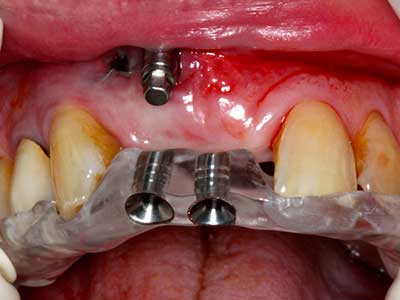

Indication: Bone splitting

Bone tissue is not simply a mineral structure but also contains a substantial proportion of collagen fibres. This means it not only has good compressive strength but also a degree of flexibility, which can be taken advantage of when performing bone augmentations. In the classical expansion procedure using bone splitting, the atrophied alveolar ridge is split longitudinally and carefully expanded after reaching an adequate osteotomy depth (Fig. 13-16), ideally without substantial removal of the periosteum (Brugnami, Caiazzo et al. 2014, Stricker, Fleiner et al. 2014). Screw and plate systems with increasing expansion distance have proven effective in separating the two bone lamellae while remaining below the fracture threshold. In general, residual bone widths of at least 3–4 mm are required (Chiapasco, Zaniboni et al. 2006) to guarantee adequate flexibility and sufficient bone coverage of the future implants. If necessary, a vertical relief osteotomy on one or both sides can improve flexibility. A combination with additional augmentation techniques, particularly on the buccal side, has been described as an alternative to the classical technique.

The splitting procedure is particularly atraumatic and there is no significant loss of dimension when using piezosaws, and there are no significant differences between implants in split jaws and implants in an alveolar ridge without a bone deficit (Chiapasco, Zaniboni et al. 2006, Danza, Guidi et al. 2009). However, sufficient continuous irrigation is essential, particularly with locally restricted and deep splitting to prevent thermal stress in the apical osteotomy regions.